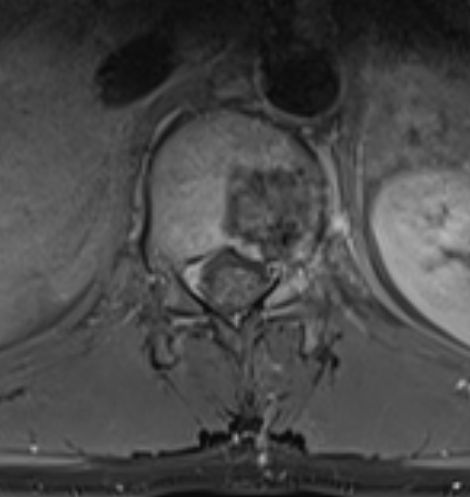

| Knochen | 36-jähriger Mann, der vor 2Jahren wegen eines blutenden "Ulkus" übernäht wurde.

Jetzt fortgeschrittenes Magenkarzinom. Gastektomie, Lymphonodektomie, Splenektomie,Ösophagojejunostomie,Y-Roux -Anastomose nach FLOT -Chemotherapie.

Das MRT zeigt Wirbelmetastasen.![]() |